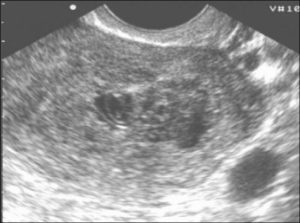

Гинеколог выявляет мягкую консистенцию органа при осмотре. Подтверждают развившийся негативный процесс клинические и биохимические анализы мочи и крови, трансвагинальное УЗИ (ультразвуковое исследование).

Проводится визуальный осмотр шейки матки и пальпация. Внутренний зев ее будет расширен, плодный остаток в наличии. УЗИ определит его объем и локализацию, а также общее состояние репродуктивных органов. Биохимический анализ крови расскажет о функционировании органов и систем пациентки.

При неполном аборте беременность больше не подтверждается различными тестами, поэтому примерно через неделю после отторжения плодного яйца необходимо сделать УЗИ, чтобы удостовериться, что в матке нет остатков эмбриональной ткани. Если остатки плодного яйца после медикаментозного прерывания беременности обнаружены, следует вовремя начать лечение.

Что делать? Лучше этот вопрос заранее обговорить с врачом. По стандартным рекомендациям УЗ-исследование после аборта выполняют на 10-14 день, но если это сделать через 5-7 дней, то есть возможность вовремя заметить признаки неполного аборта и назначить лекарственные средства.

Но так или иначе, лучше сделать УЗИ матки. Платно можно и без направления врача. А по его результатам будет понятно — нужно ли лечение, в том числе хирургическое.

При появлении первых симптомов, вызывающих опасение, женщина должна обратиться в больницу. Основными методами диагностики состояния являются гинекологический осмотр и УЗИ.